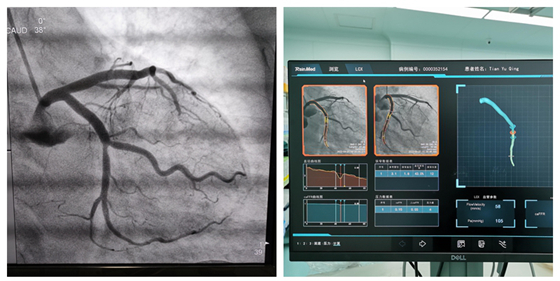

回旋支造影结果 回旋支FFR检测结果

完善准备工作后,心血管内科医疗团队携手麻醉手术部进行FFR检查,经计算得出FFR值为0.95(>0.8),暂无支架植入指征,建议强化药物治疗。经强化药物治疗,患者病情平稳,未发作心绞痛。